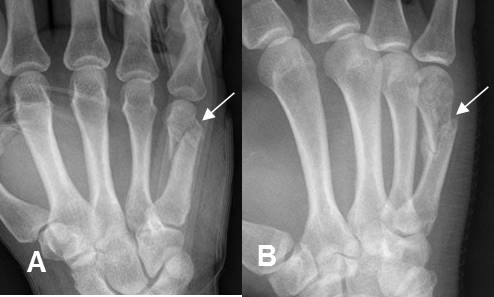

Fig 178. Fractura del boxeador.

A: Rx AP de mano. Fractura oblicua en la cabeza del 5º metatarsiano.

B: Rx oblicua de mano. Fractura en la diáfisis del 5º metatarsiano.